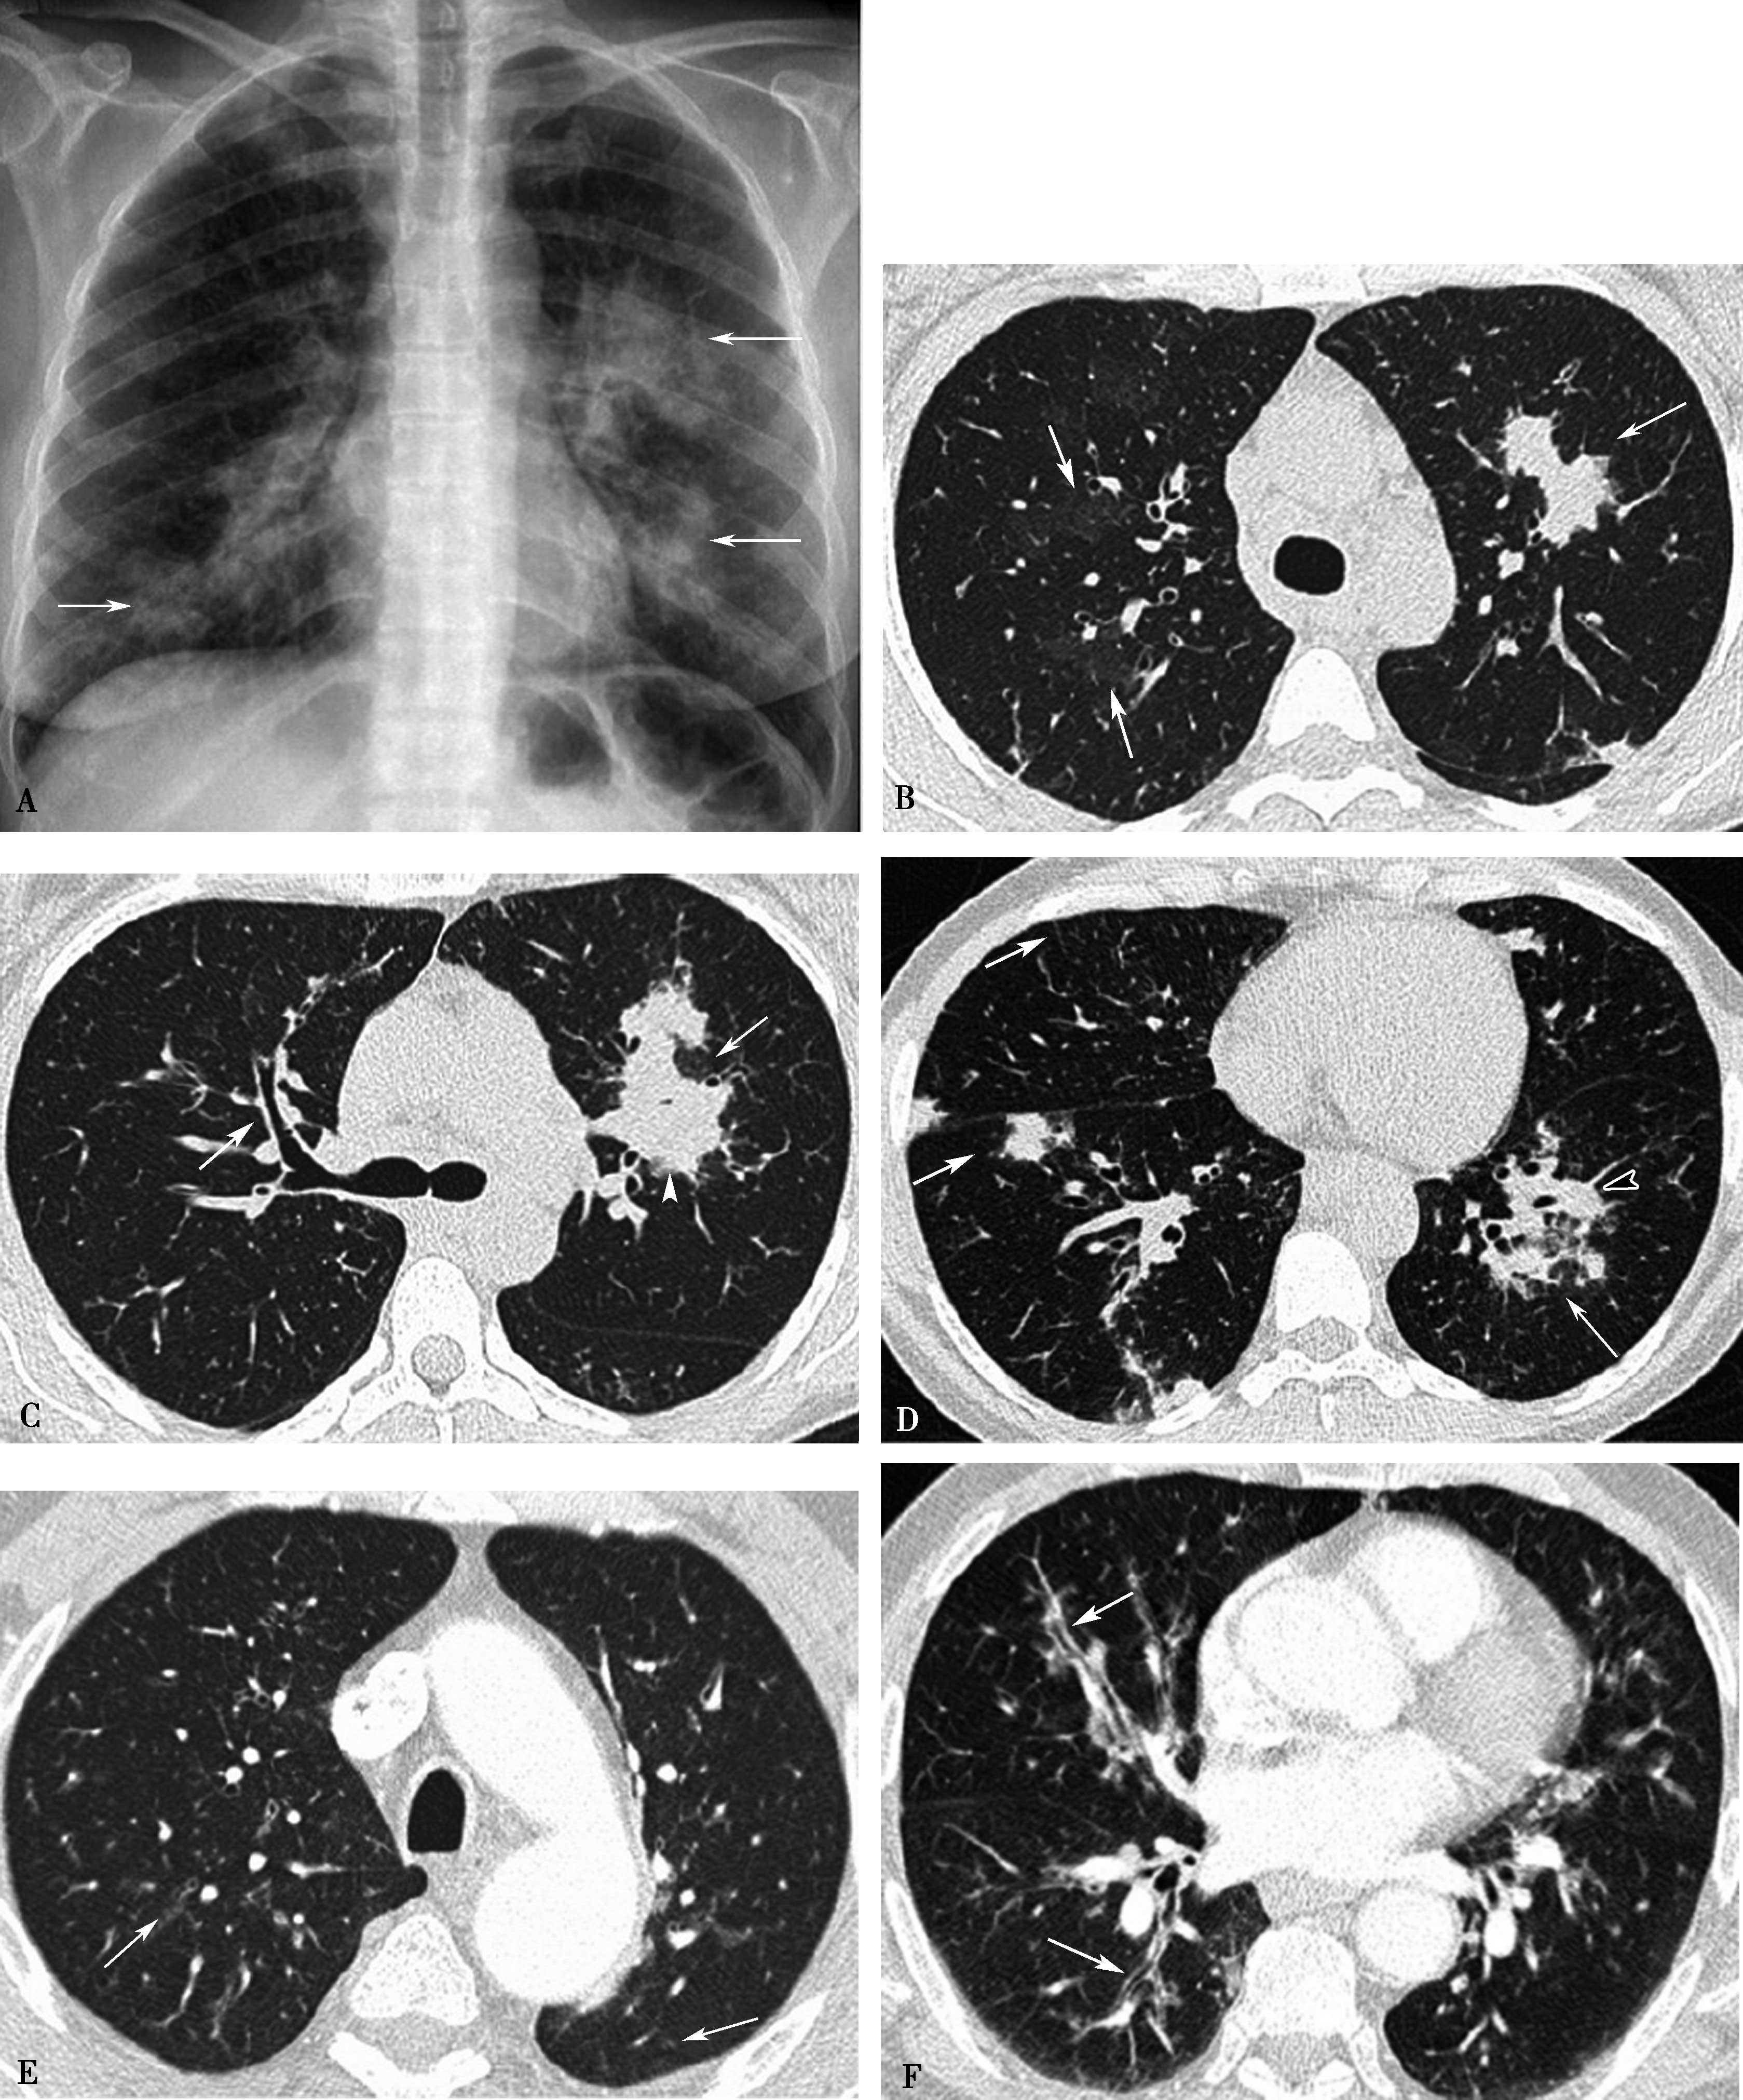

高分辨率CT(平扫)对诊断有重要价值。显示肺实质多发性斑片状、大小不等结节及空洞形成,主要分布两肺中下野,多发性/多样性(不规则,多发,大小不等)为其特点,并存胸膜反应,胸腔积液(图8-5-6)。

图8-5-6 坏死性肉芽肿性血管炎(韦格纳肉芽肿)

A.胸部X线片,两肺多发结节,不规则空洞形成(↑);B~D.横断图像,两上、下肺多发不规则结节肿块,大小不等,不规则空洞形成,壁薄厚不一,边缘不规则,液平形成;病理检查:E.肺小血管横断面,显示炎性细胞浸润累及部分血管;F.肺小血管纵切面,炎性细胞浸润,部分管壁破坏。CT诊断:韦格纳肉芽肿(病理证实为坏死性肉芽肿性血管炎)